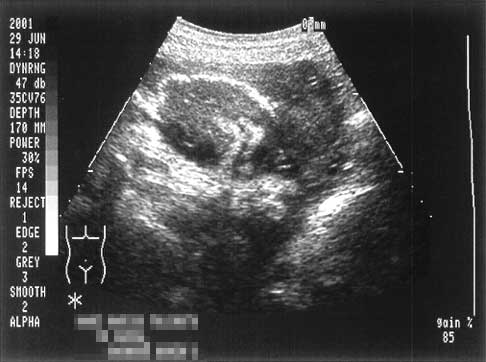

Bay's Photo Diary - June 29, 2001

予定日を一日過ぎました。どうやらまだまだでてきたくないよう。。